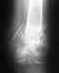

В июне месяце было сделано КТ:

КТ исследование левой стопы выполнено в многоспиральном режиме сканирования с толщиной среза 1.0 мм.Определяется фрагментирование медиальной сесамовидной кости 1 пальца.Края смежных фрагментов склерозированные, неровные. Выраженый отек мышцы сухожилия приводящей большой палец.

Костная структура костей не изменена.

Соотношение костей в суставах не нарушено.

Суставные щели рамномерные.

Полости сустанов без наличия патологического содержимого.

ЗАКЛЮЧЕНИЕ:

КТ-признаки несросшегося перелома сесамовидной кости 1 пальца левой стопы. Сесамоидит.

ЭЭД- 5.3 мЗв

21.06.13